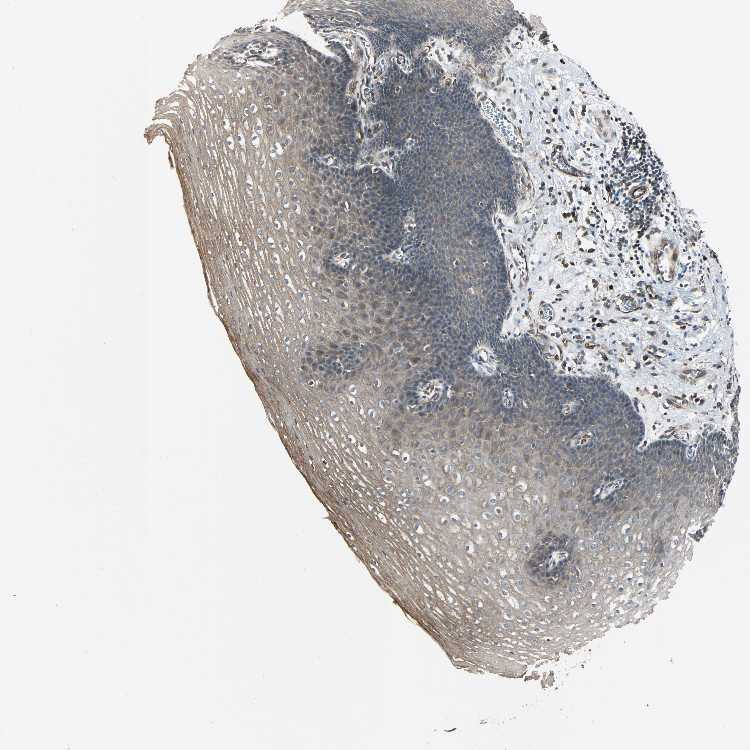

ESOPHAGUS - Antibody stainingi

Antibody staining in the annotated cell types in the current human tissue is reported as not detected, low, medium, or high, based on conventional immunohistochemistry profiling in selected tissues. This score is based on the combination of the staining intensity and fraction of stained cells.

Each image is clickable and will lead to virtual microscopy that enables deeper exploration of all samples and also displays staining intensity scores, fraction scores and subcellular localization as well as patient and tissue information for each sample.

Antibody HPA006616

Squamous epithelial cells Medium